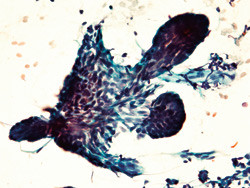

Cytologisk diagnostikk kan vise seg fordelaktig sammenliknet med histologisk diagnostikk av ikke-melanom hudkreft. Det viser en norsk studie.

Studien omfattet 231 cytologiske utstryk som ble fremskaffet ved hjelp av to ulike prøvetakingsmetoder, dvs. skrape- eller trykkteknikk (1). Utstrykene ble både farget med Papanicolaou- og May-Grünwald-Giemsa-fargemetode. Parallelle prøver ble tatt fra samme lesjon, og de cytologiske og histologiske preparatene ble undersøkt av en uavhengig patolog uten tilgang til kliniske opplysninger. Cytologisk og histologisk diagnose ble sammenliknet, og histologisk diagnose ble oppfattet som gullstandard i studien.

Ved skrapeteknikk fant vi samsvar mellom cytologisk og histologisk diagnose i 95 av 100 utstryk fra basalcellekarsinom og i 47 av 54 utstryk fra aktinisk keratose når resultatene fra begge fargemetodene ble slått sammen. Det var ingen signifikante forskjeller mellom de to fargemetodene.

Trykkteknikken resulterte i mange utstryk med dårlig kvalitet og viste diagnostisk samsvar i kun halvparten av tilfellene. Resultatet fra undersøkelsen viser at cytologisk diagnose ved skrapeteknikk av basalcellekarsinom og aktinisk keratose har høy sensitivitet og spesifisitet og at metoden differensierer godt mellom de to formene for hudpatologi.